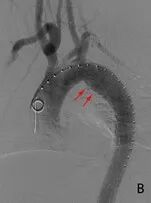

支架在预定位置展开,既完美覆盖了血管内膜的破口,将肆虐的血流重新导入真腔,又巧妙地为通向大脑和上肢的重要分支血管留出了通道。

数小时后,当造影显示支架位置完美,主动脉血流恢复通畅,所有人都松了一口气——这颗“不定时炸弹”终于被成功拆除。

主动脉支架植入后,破口消失,主要血管分支通畅